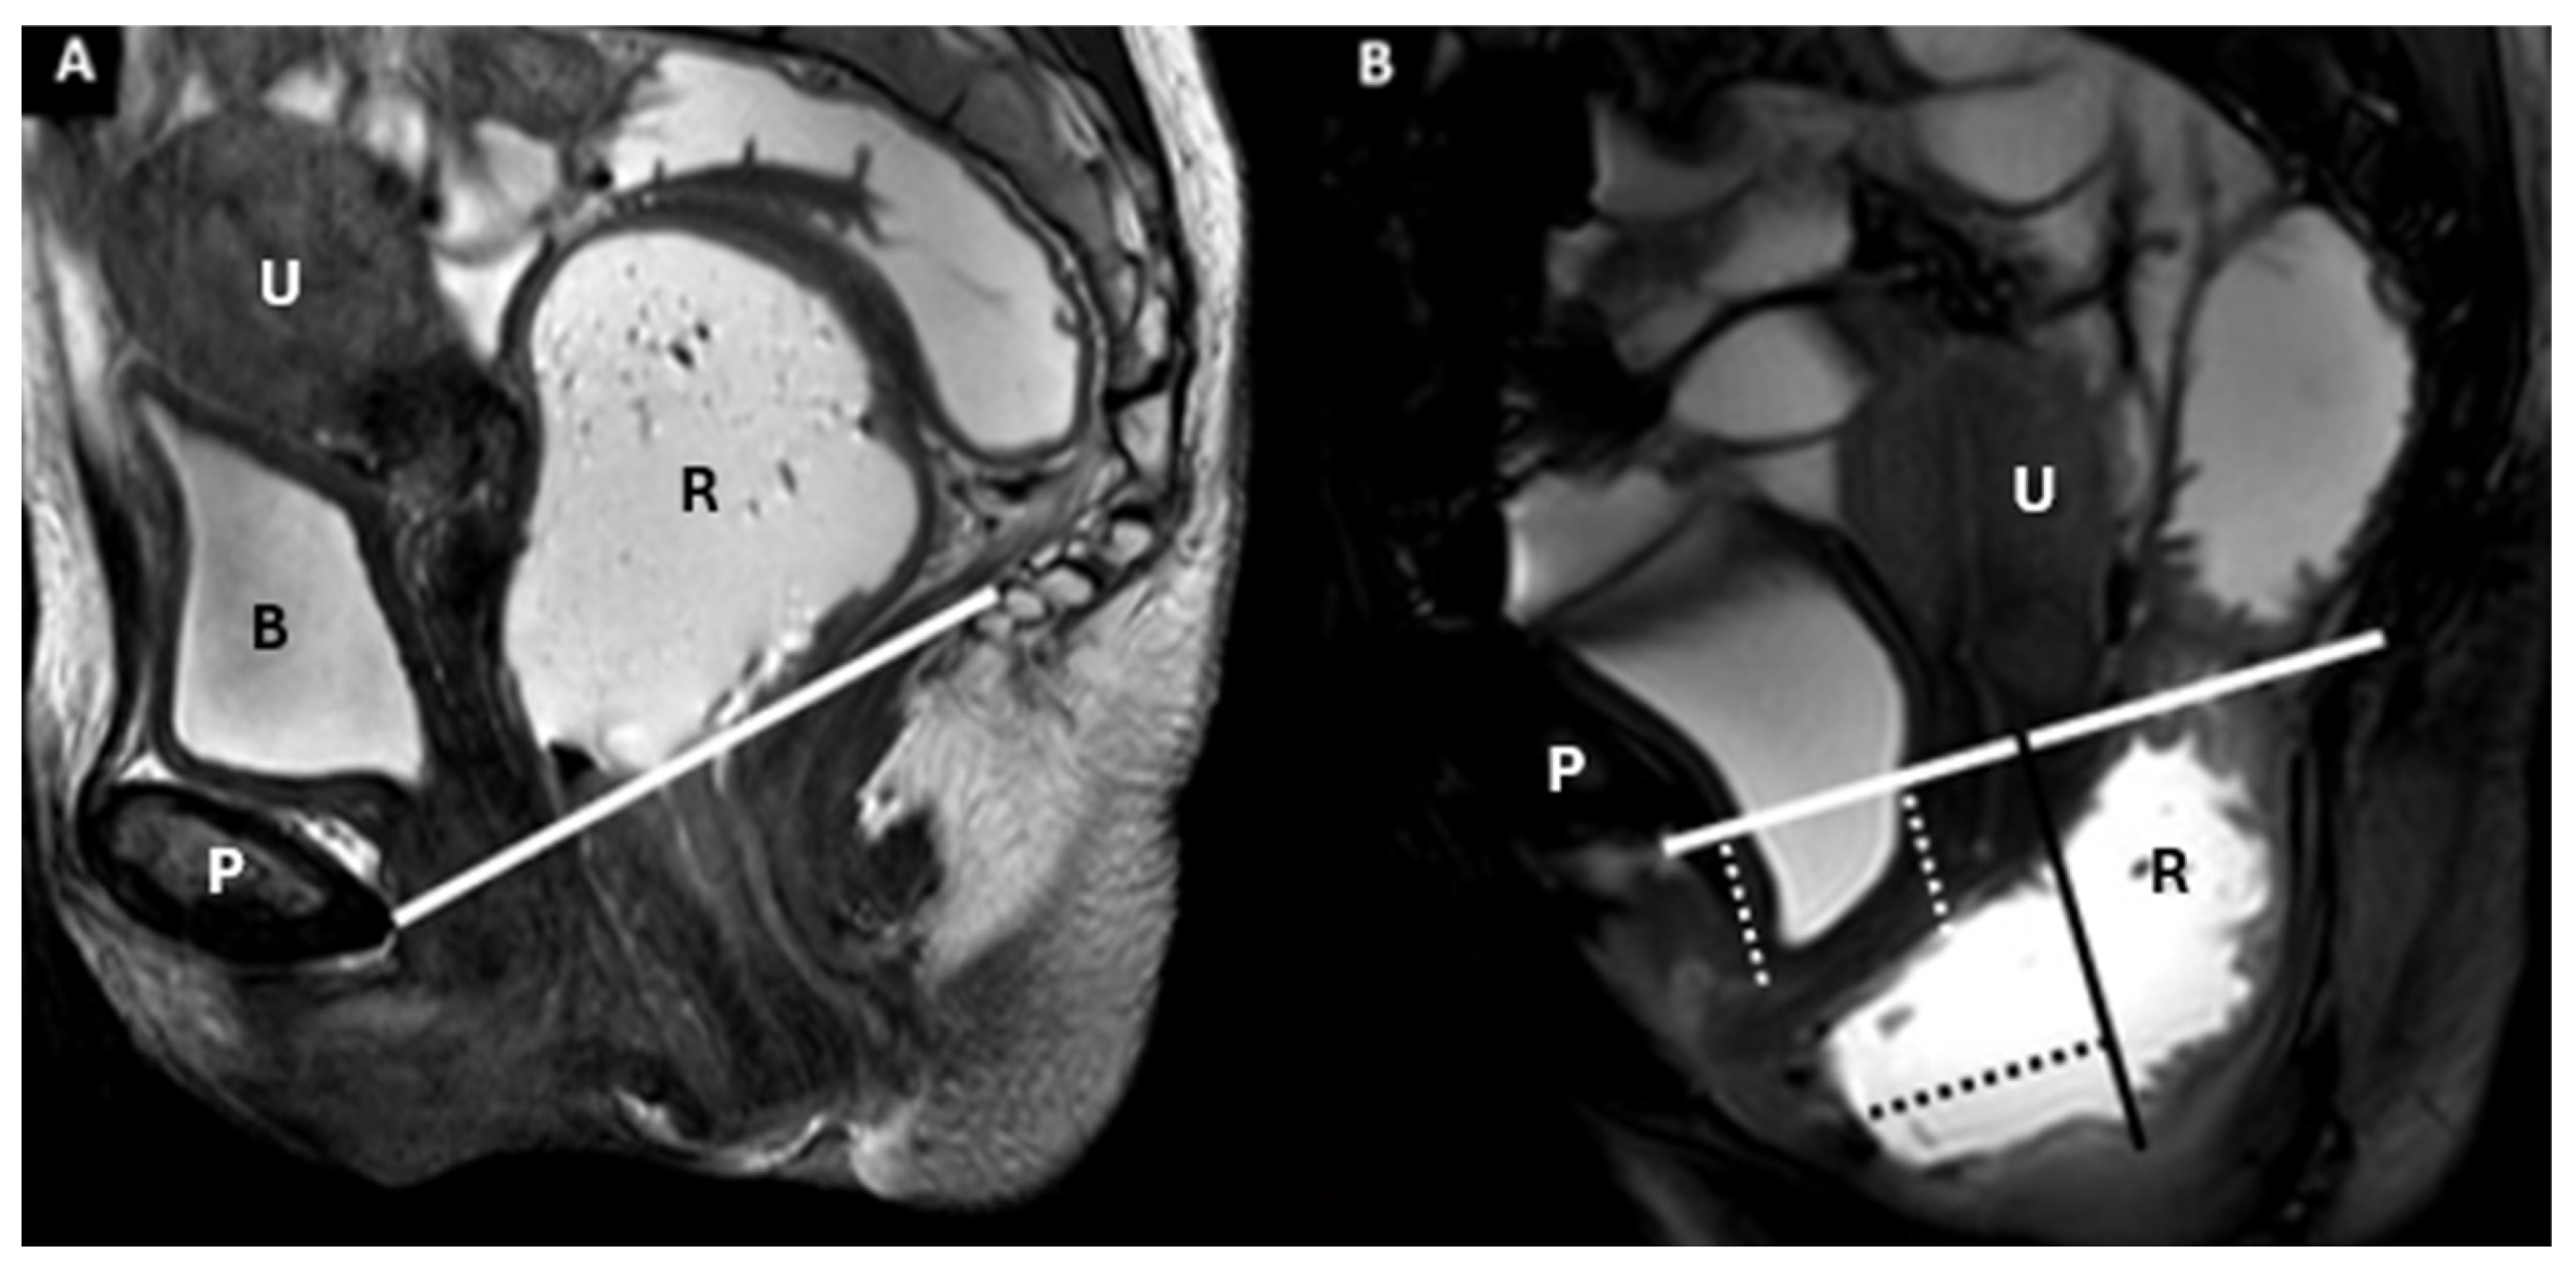

| Pubococcygeal Line (PCL) | Line from the inferior pubic border to the last coccygeal joint | Baseline for measuring organ descent | PCL Compartment Staging Stage 0: Above PCL Stage I: Descent <3 cm below PCL Stage II: Descent 3–6 cm below PCL Stage III: Descent >6 cm below PCL Stage IV: Complete organ prolapse |

| Rectum, anal canal | Rectovaginal fascia, perineal body | Rectal intussusception/prolapse | Extent of rectal mucosa relative to rectocele/anal canal | Mild: 1–2 cm Moderate: 2–4 cm Severe: >4 cm |